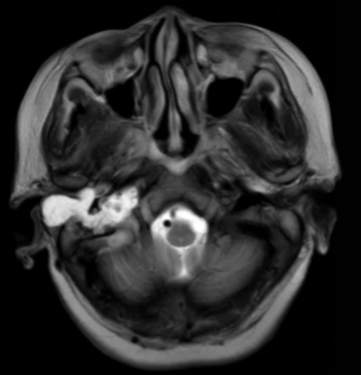

(2023-05-15 10:00,本院)行磁共振(颅脑)检查提示:右侧乳突区异常信号,考虑恶性、软骨来源肿瘤,软骨肉瘤可能性大。(集体讨论意见);脑内散在多发缺血灶。

(2023-05-12 10:15,本院)行CT(颅脑)检查提示:右侧颞骨广泛骨质破坏,伴巨大软组织肿块,性质待定,考虑肿瘤性病变,颈静脉球瘤?软骨源性肿瘤?请结合临床及病理进一步明确。